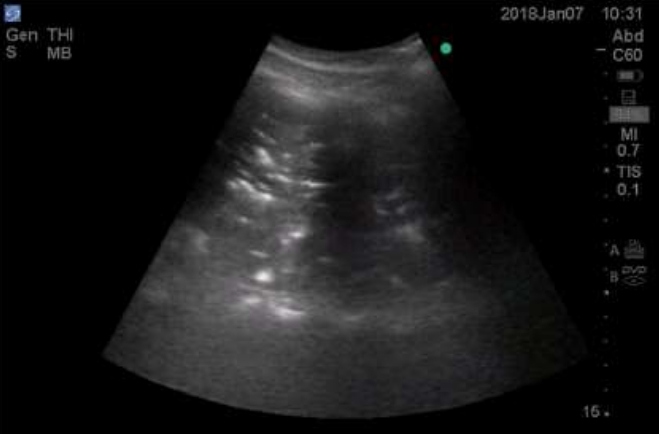

Consolidation in lung ultrasound may be identified as tissue-like echogenicity. Small consolidations (some authors refer to it as subpleural consolidations [6], however some believe the name to be inappropriate [14]) are echo poor regions approximately 0.5 cm in diameter with the presence of shred sign- the irregular border in between the consolidated and aerated lung tissue [15]. Air bronchograms are hyperechoic artifacts within the consolidation and are said to be dynamic if they move centrifugally more than 1 mm during inspiration [16] (Figure 1and 2).

Figure 1: Lung consolidation showing tissue like consistency with air bronchogram.